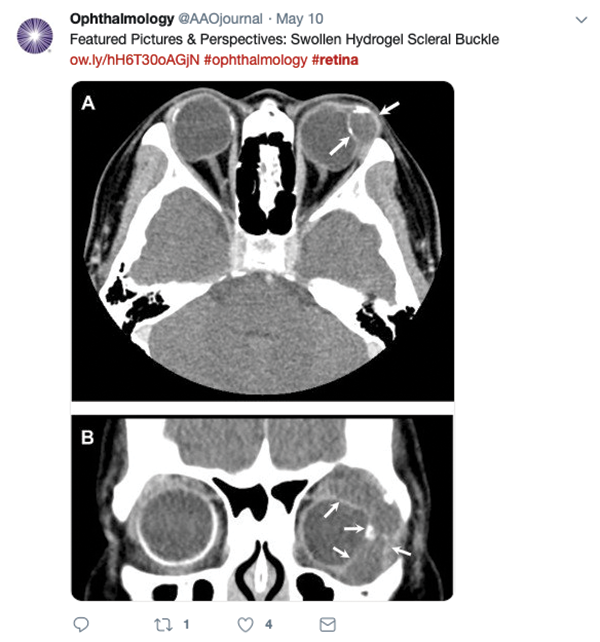

TWEETS OF NOTE